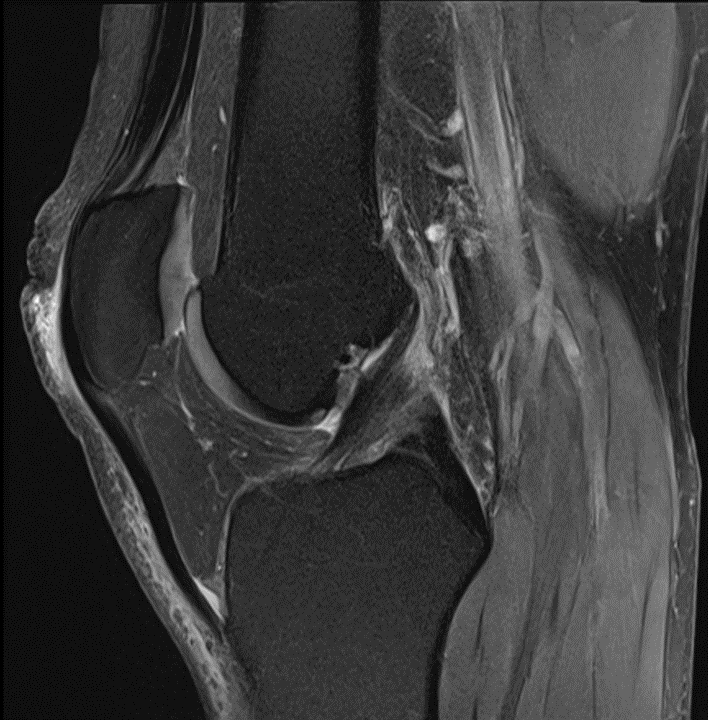

Sie sehen folgendes MRT-Bild eines Patienten unter Therapie mit Ipilimumab. Um welches Krankheitsbild handelt es sich und welche andere Untersuchung könnte man durchführen um andere Nebenwirkungen des Medikamentes auszuschließen?